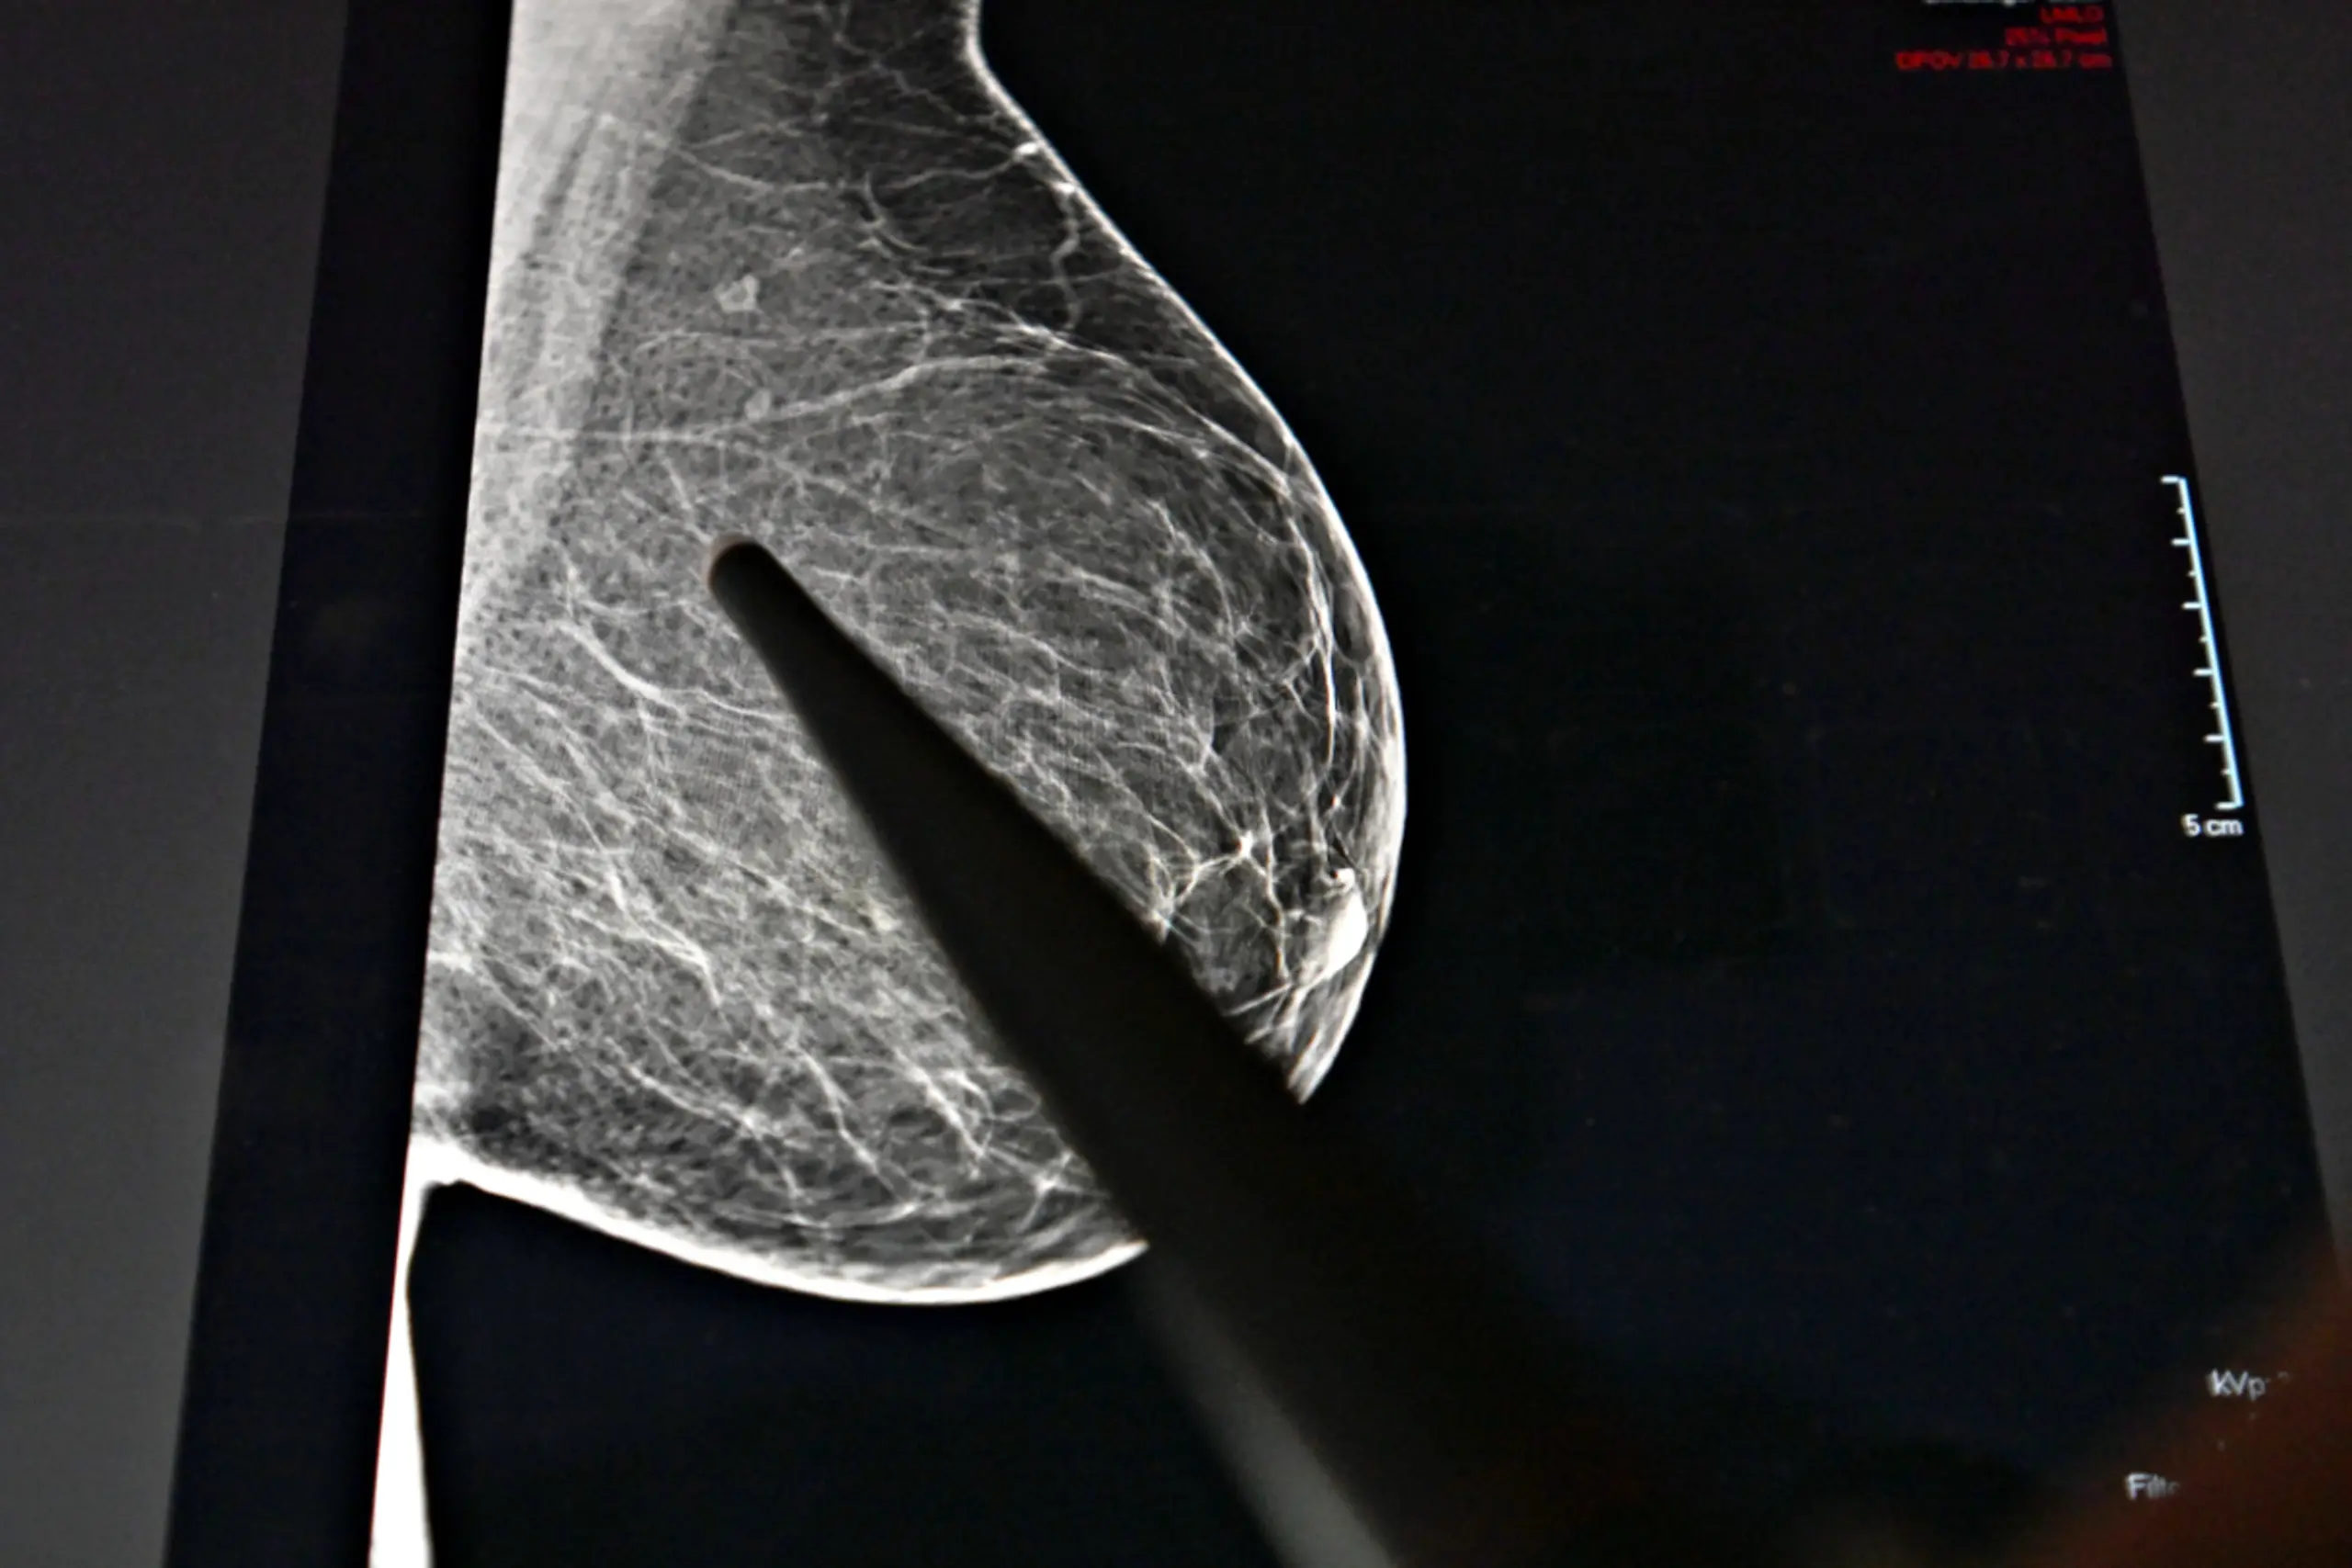

++ THEMENBILD ++ Illustration zum Thema "Mammografie / Brustkrebsvorsorge / Brustkrebs-Früherkennung / Radiologie / Röntgen / Frauen /Gesundheit" - Ein digitales Bruströntgenbild, aufgenommen am Mittwoch, 19. November 2025.

Früherkennung mit regelmäßigen Mammografie-Screening-Untersuchungen stellen ein wirksames Mittel zur Verhinderung von Brustkrebs im Spätstadium und dementsprechend auch von Todesfällen dar. Doch es gibt auch ein großes Präventionspotenzial. "Mehr als ein Viertel der durch Brustkrebs verlorenen gesunden Lebensjahre sind auf sechs veränderbare Risikofaktoren zurückzuführen, darunter ein hoher Konsum von rotem Fleisch, Tabak, ein hoher Blutzuckerspiegel (Diabetes; Anm.) und ein hoher BMI (Adipositas; Anm.) - was wichtige Möglichkeiten zur Prävention bietet", heißt es vonseiten des "Lancet".